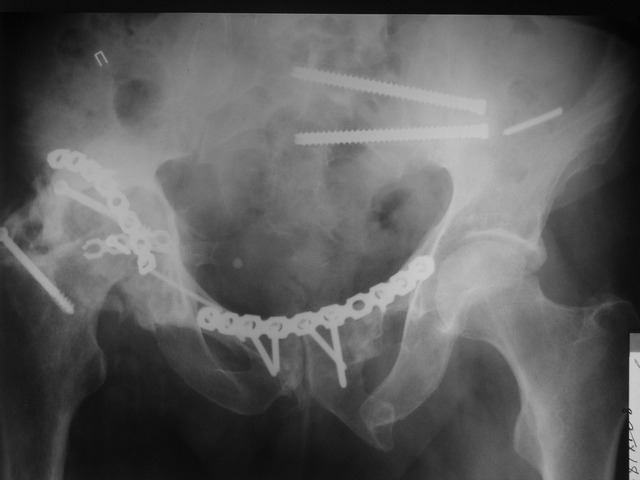

Пациент 49 лет, паровозная травма 23.2.2006, получил вертикальная

нестабильное повреждение таза, разрыв левого крестцово-подвздошного

сочленения, перелом лонной, седалищной костей слева, T-образный

оскольчатый перелом правой вертлужной впадины с переломом заднего

края, вывих правого бедра, посттравматическая пояснично-крестцовая

плексопатия с обеих сторон, паралич мышц правой голени.

В день травмы - вправление вывиха, скелетное вытяжение, 14.3.2006

чрескостный остеосинтез таза. 20.4.2006 остеосинтез правой вертлужной

впадины пластинами, осложнившийся нагноением межмышечной гематомы

правой ягодичной области. Получал консервативное лечение, было

достигнуто полное заживление раны. 24.7.2006 введены илиосакральные

винты слева. С декабря 2006 года и по настоящее время ходит на

костылях без опоры на правую ногу. Планируется THA. Помогите

определиться с вариантом костной пластики? И какую укрепляющую

конструкцию использовать?